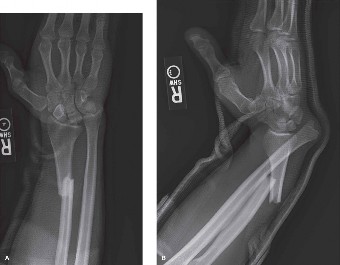

![Image](/media/upload/7b28c8c3-e130-49b6-9d4b-a0d5247227e.jpg)

*A graphic demonstrating the typical appearance of a Galeazzi fracture-dislocation on plain radiographs, illustrating the displaced radial shaft fracture and dorsal dislocation of the ulnar head relative to the radius on the lateral view.*